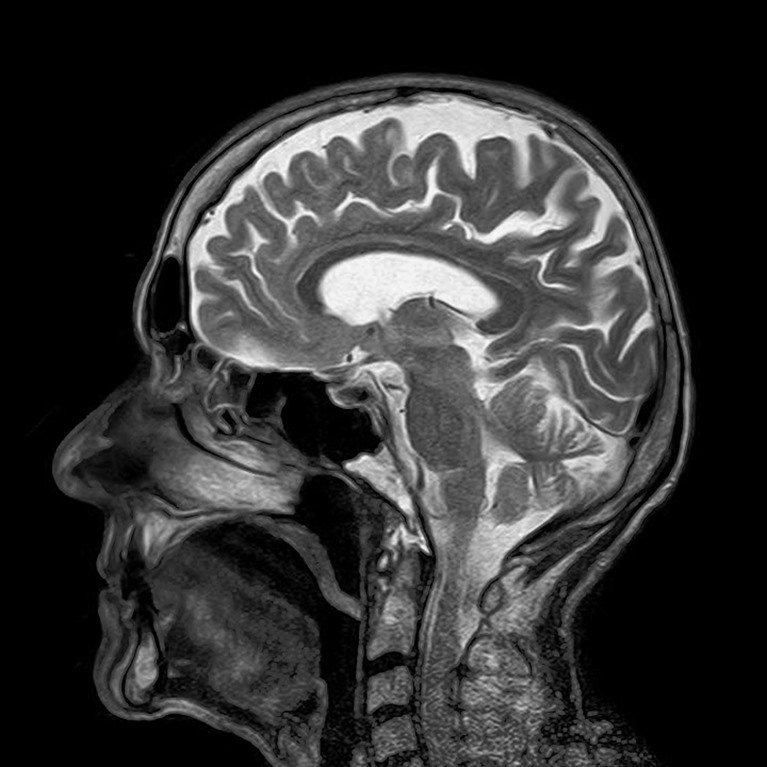

9 jaar geleden  - MRI-scans zijn veelbelovend voor het vroegtijdig herkennen van een verslaving bij adolescenten, meldt de website van Oregon State University. De scan vertaalt de signalen van de hersenen in beelden die inzicht bieden in de hoogte van het risico op een verslaving. Herkenning op vroege leeftijd zorgt er voor dat er ook op tijd hulp kan worden aangeboden.